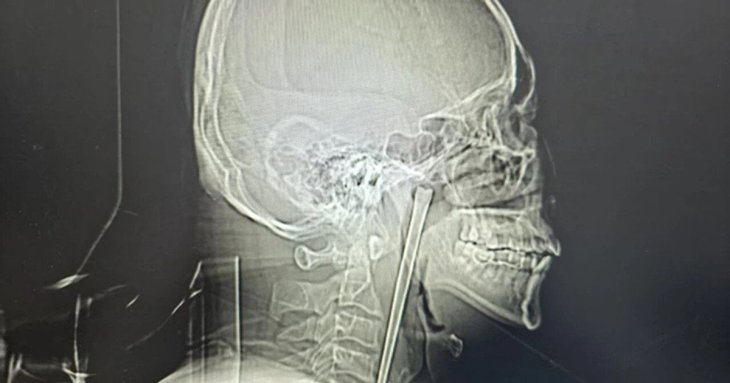

46-річний пацієнт звернувся до лікарні зі скаргами на сильний біль у горлі та відчуття стороннього предмета. Після рентгену лікарі виявили довгий металевий стрижень, що застряг у глотці.

Після обстеження лікарі розробили менш інвазивний метод — видалення через ротову порожнину без розрізів на шиї. Під час операції спеціалісти змогли обережно витягти паличку повністю.